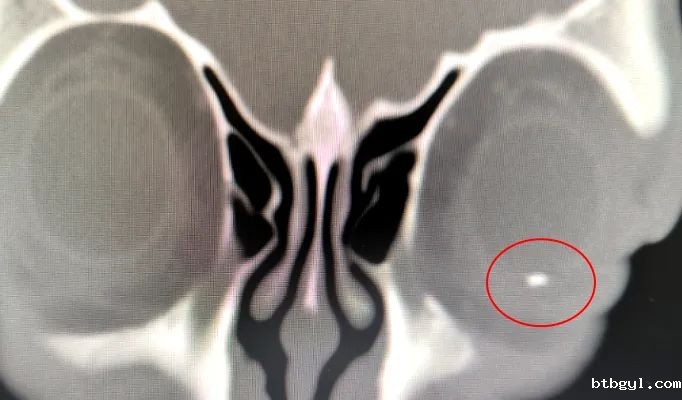

眼科耳鼻咽喉科主任、副主任医师胡习莲为甘大叔作了详细检查。经眼部CT、眼部B超检查,发现甘大叔眼球里竟存在一大小约4mm的异物。

眼部CT图像

这枚异物已经造成甘大叔左眼晶状体形态异常、全眼球炎症。若不处理该异物,该异物将作为一枚“不定时炸弹”,反复诱发眼内炎症,导致患者痛苦加重,甚至摘除眼球。综合考虑下,胡习莲主任决定为甘大叔进行手术,将异物取出。